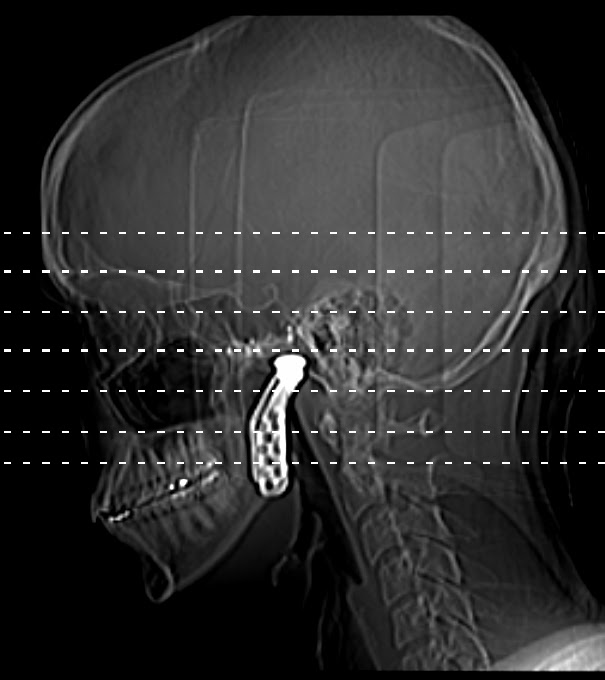

Blogged Up Body Blogged Up Life Radiology What Is A 5 Day Sitz Marker Study our team of specialized doctors, nurses and technologists perform sitz marker studies to see how fast food is moving through the intestines. a colon transit study is a diagnostic test that will allow your doctor to evaluate the function of your colon. Patient has a flat plate. A sitz marker study is most often used with patients who. What Is A 5 Day Sitz Marker Study.

Reading the results Medifactia What Is A 5 Day Sitz Marker Study our team of specialized doctors, nurses and technologists perform sitz marker studies to see how fast food is moving through the intestines. radioopaque marker testing distinguishes constipation subgroup such. Patient continues their normal routine as the capsule dissolves and releases the markers inside their digestive tract. For the study, the patient swallows a capsule containing. what is. What Is A 5 Day Sitz Marker Study.